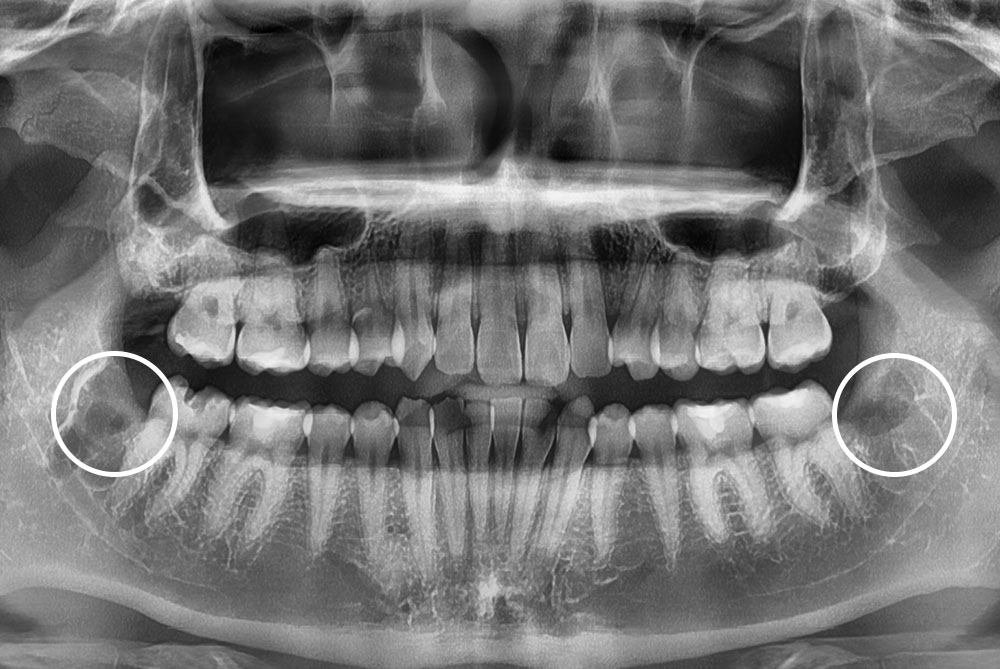

[사랑니] 매복 사랑니 발치

치료후 : 2022-08-09

세종치과는 구강악안면외과학 박사이신 원장님이 발치하는 치과입니다.